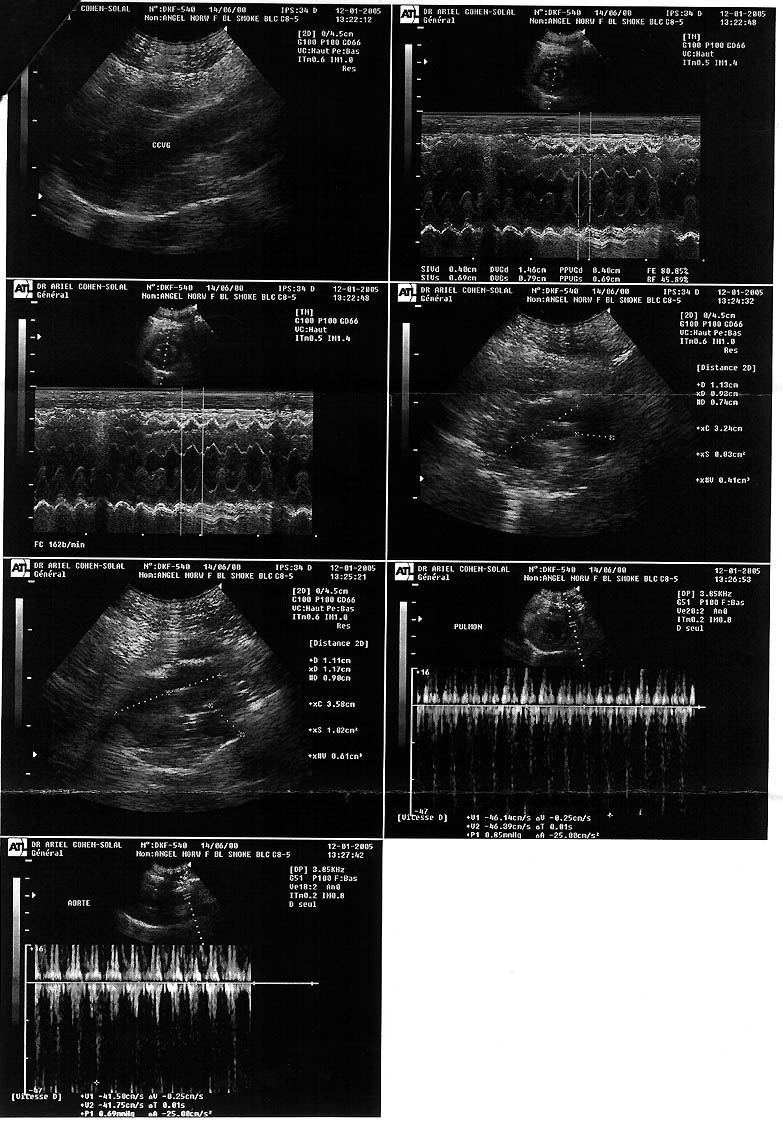

| Holy Angel av Skara Brae*CH - (F) |

| GIC Kong Salomon Felis Jubatus*DK S*Aristo Limaz Irma |

Sarah Runzis | 18/06/2000 | first premier |

none aucune |

normal | 4.5 years / ans |